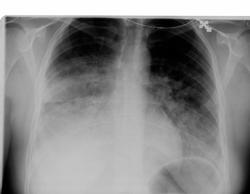

молодая девушка 27 лет

Поступила с жалобами на сердцебиение, кашель с пенистой мокротой,одышку. На Д учете не сотоит.

снимки от 09.07 10.07 12.07 соответственно

А R-грамм в боковых проециях нет? Интенсивное затенениев нижних полях с 2-сторон , более выраженное справа. Резковыраженная положительная динамика за сутки с 9.07. по 10.07., а на моммент 12.07. практически норма. Имеем дело с острым процессом, скорее всего с отёком лёгких, который разрешился на фоне проведённой терапии.Пока такая версия.

Нам представился случай показать и отразить динамику отека легких у молодой больной с пароксизмом наджелудочковой тахикардии ЧСС до 200 в 1 мин.медикаментозно купированний.Синдр.WPW.На Д учете не состоит.

Можете ли вы объяснить,чем обусловлено, то что  при отёке лёгких в данном случае, имеет место неодинаковое по интенсивности поражение правого и левого лёгких?

Скорее всего вы правы, вероято сказалось то , что справа гидростатическеое давление из-за положения тела, в сосудах было выше чем слева, по этой причине такая ассиметрия по интенсивности проявлений отёка. Но, это только версия ( иного объясения, я просто не могу представить).Может быть кто-то сможет объяснить это явление по другому.

Объяснить трудно,но отек часто несимметричен.